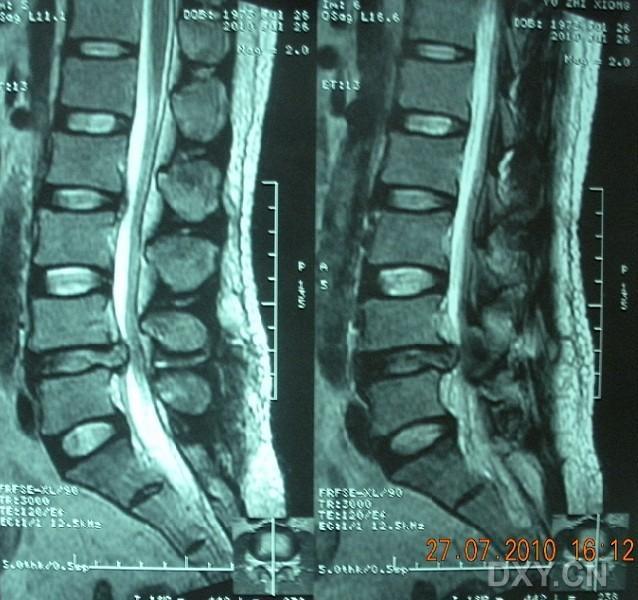

如有下列情况,是需要做固定的:

1、腰椎间盘突出合并腰椎滑脱、腰椎不稳的;2、腰椎间盘突出合并椎管狭窄(多数有间歇性跛行的症状),需行大范围减压的;3、术后腰间盘突出复发二次手术的;4、高位的腰椎间盘突出;5、二个以上多节段的腰间盘突出,手术需要广泛减压;

6、极外侧型间盘突出,手术需要破坏小关节的;

7、年龄大于45岁,需要承担较强体力劳动的;

我们采用4cm小切口显微镜下单纯腰椎间盘突出症经开窗摘除髓核手术,患者第二天即可下床行走,不仅解决了腰腿痛问题,同时费用明显降低。